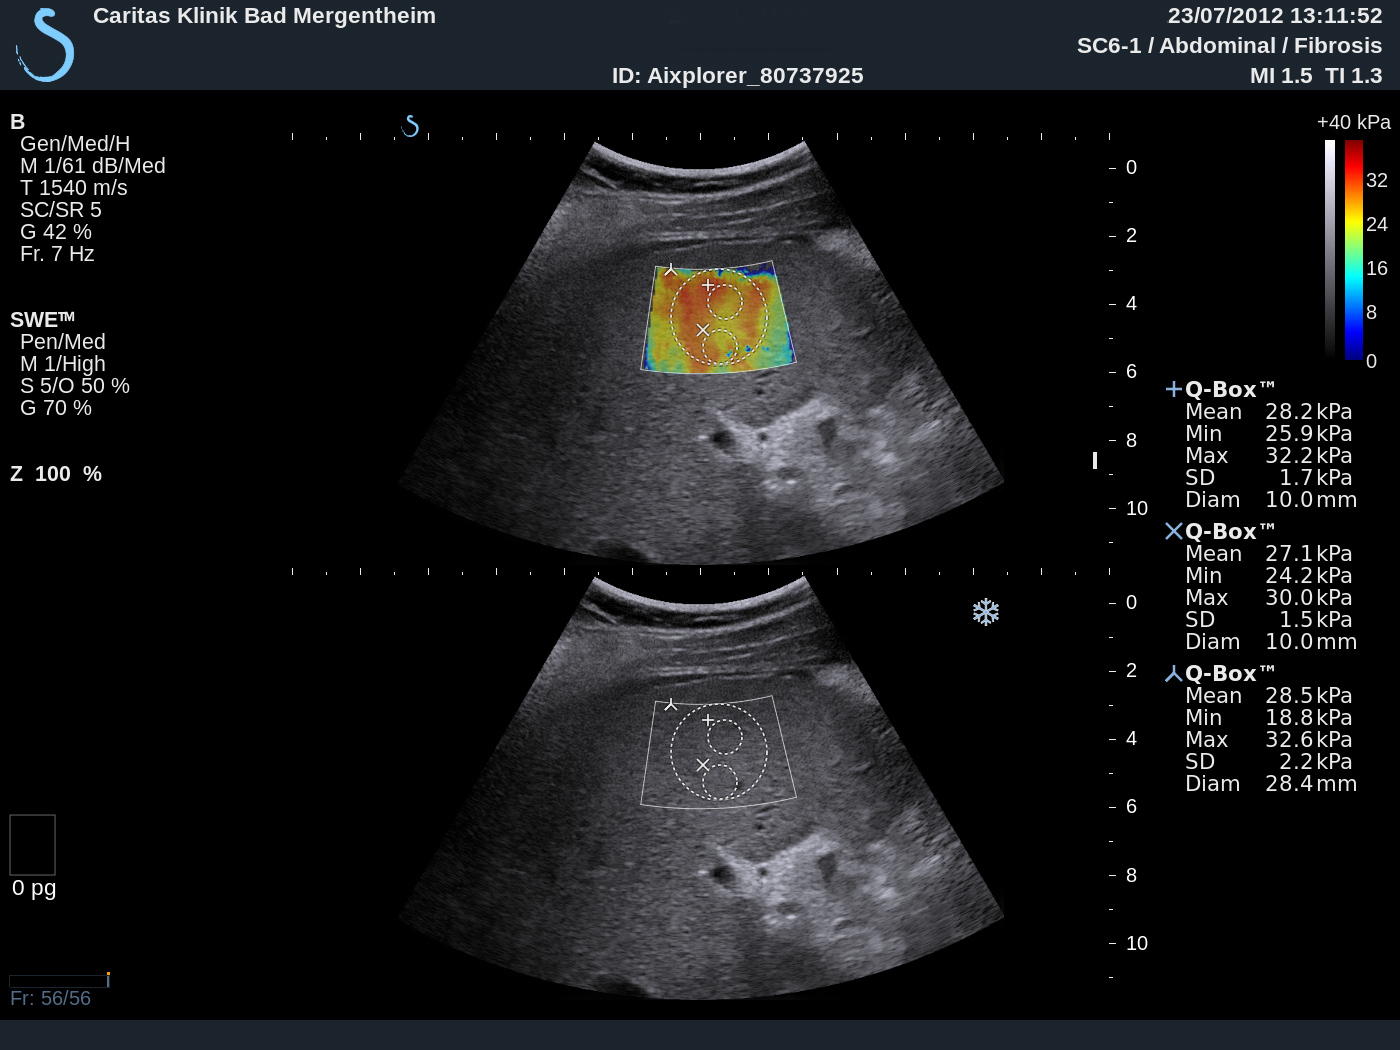

1 Case report We report on shear wave elastography using Supersonic Imaging (SSI) from a practical point. The procedure was repeated three times of three different scanning views in order to acquire three valid independent SWE™ maps. Examples are shown in Figure 1. The case reports in healthy subjects, patients with intermediate fibrosis and liver cirrhosis were summarized and analyzed to discuss basic principles, imaging acquisition, data reproducibility, advantages and limitations of this method as part of the Shear Wave Elastography Research Group activities (SWERG).

3.2.6 SWE™ stiffness quantification

Once the SWE™ map is satisfactory, freeze and select the Q-Box™ measurement tool. Resize its diameter to 15-20 mm if needed, place it preferably at the center of the SWE Box, over an area of relative homogeneous elasticity, at a depth of 3-5 cm; do not place it over an area with missing SWE™ pixels. On recent software versions of Aixplorer® liver package, a Stability Index has been added as an indicator of SWE map homogeneity and temporal stability. This index is displayed while positioning the built-in Q-Box™ quantification tool. A Stability Index below 90% should lead to the rejection of the Q Box™ location, and push the operator to find a better location. In the event no satisfactory location can be found on a given frozen SWE™ map, a new SWE™ acquisition should be performed.